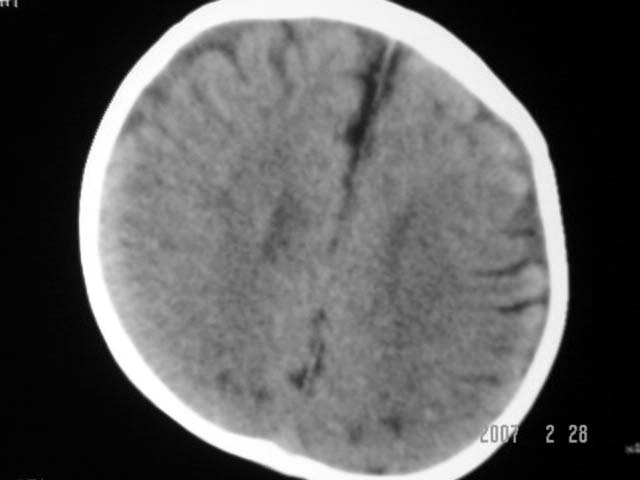

标题: PED0015:男,8M,发现不会坐立及神情异常,前囟已闭,双眼斜视, [打印本页]

标题: PED0015:男,8M,发现不会坐立及神情异常,前囟已闭,双眼斜视,

脑回较深,白质范围小,灰白质比例失调。余未见明显异常。

考虑:脑白质发育不良,必要时请做mri进一步检查。